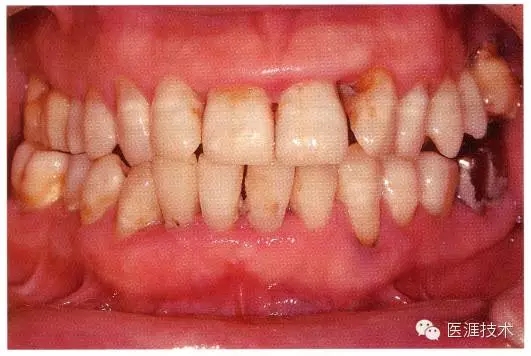

健康牙周組織的牙齦邊緣呈珊瑚粉,邊緣牙齦略呈圓弧狀。牙間可見三角形的牙間乳頭,牙齦邊緣相連呈貝殼形。

附著齦與游離齦相連時(shí),有時(shí)有游離齦溝存在(成人的30~40%)。

附著齦通過膠原纖維牢固結(jié)合骨骼與牙骨質(zhì),因此可見不可動、硬而緊繃的點(diǎn)彩(橘皮樣點(diǎn)狀凹凸)。

從牙齦牙槽粘膜到根尖有牙槽粘膜。牙槽粘膜為暗紅色,與骨骼結(jié)合較松,故可動。

健康且正常的牙周組織臨床圖像

50歲女性的健康口腔內(nèi)部

圖為50歲女性,無特殊全身疾病,不抽煙。持續(xù)保養(yǎng)6年。無填充物等問題,依照患者本人要求持續(xù)觀察。牙周組織臉頰側(cè)雖見部分萎縮,但X線牙片顯示牙間無骨吸收現(xiàn)象,保持著比較健康的狀態(tài)。